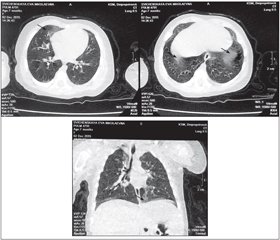

Заключение по КТВР ОГК (рис. 1): на правой верхушке, в прикорневых зонах, в дорсальных отделах обоих легких, в средней доле справа и в язычковых сегментах слева определяются участки в виде «матового стекла», в передних отделах более распространенные. Органы средостения без особенностей. Заключение: КТВР — признаки интерстициального поражения легких.

Таким образом, данное клиническое наблюдение иллюстрирует случай интерстициального заболевания легких, которое дебютировало уже с первых месяцев жизни ребенка, что подтверждает современный взгляд на ИЗЛ как на возможную проблему детского возраста. Своевременная диагностика на ранних, еще обратимых, стадиях заболевания и адекватная терапия могут предотвратить прогрессирование болезни и улучшить прогноз. Наличие симптомов «матового стекла» по данным КТВР у данного пациента, отсутствие стойкой прогрессирующей гипоксемии, быстрый положительный ответ на системную кортикостероидную терапию позволяют надеяться на благоприятный прогноз течения заболевания с возможным полным выздоровлением. Учитывая то, что патологический процесс происходит в развивающемся легком, прогноз детских форм ИЗЛ лучше, чем у взрослых. Настороженность врачей общей практики по поводу данной патологии должна иметь место в первую очередь при наличии респираторных нарушений (тахипноэ, одышки) у детей раннего возраста при отсутствии признаков острого инфекционного процесса, при отягощенном семейном анамнезе по ИЗЛ, при наличии типичных потрескивающих хрипов при аускультации над легкими ребенка и отсутствии других пневмонических диагностических критериев, в том числе данных рентгенографии ОГК. В этих случаях требуется проведение КТ ОГК с высоким разрешением, которую можно считать альтернативой диагностической биопсии легкого.